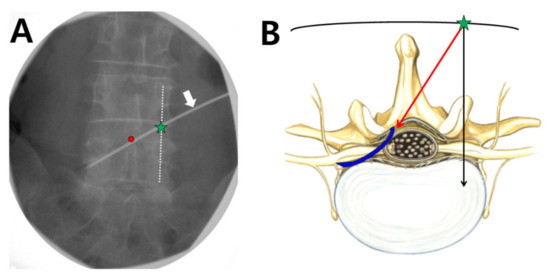

2.2.1. Insertion of the Guide Needle for a Contralateral Interlaminar Retrograde Foraminal Approach

By using caudal tilt on the fluoroscopic view, we obtained a single contour of the upper endplate of the target vertebra. The target interlaminar space was checked in an anteroposterior fluoroscopic view. To simulate the guide needle and balloon catheter pathway, a surface marker (white arrow in Figure 2A) was positioned between the lower portion of the ipsilateral pedicle, where the corresponding symptomatic spinal nerve exits, and the interlaminar epidural opening site over the interspinous process (red dot in Figure 2A). The entry point of the guide needle was at the point where this simulated line and the contralateral longitudinal pedicular lines (dotted line in Figure 2A) intersected (green star in Figure 2A). Lidocaine (1%, 1 mL) was introduced at the entry point (green star in Figure 2B), and a 16-gauge guide needle was inserted and advanced in a medial direction (red arrow in Figure 2B) until it touched the bone at the spinous process. After it touched the bone, it was walked off and advanced across the midline to the ipsilateral epidural space using the ‘loss-of-resistance’ technique, and the needle tip was advanced to the point beyond midline to the ipsilateral side. When the needle was sufficiently advanced, the lateral and anteroposterior views were checked to confirm the accurate position of the needle. Similarly, access to the ipsilateral epidural space via a CIRF approach can be performed at the same level (i.e., L5–S1).

Figure 2. Determining the entry point and catheter pathway on the fluoroscopic anteroposterior view. (A) A simulated surface marker (white arrow) positioned between the lower portion of the ipsilateral pedicle, where the corresponding symptomatic spinal nerve exits, and the interlaminar epidural opening site over the interspinous process (red dot). The entry point of the guide needle (green star) is the point at which the contralateral longitudinal pedicular lines (dotted line) and the simulated surface marker intersect. (B) Schematic cross-sectional drawing of the route of the guide needle and foraminal balloon catheter. The red arrow shows the direction of the needle from the needle entry point (green star); this must cross the midline to ipsilateral epidural space, otherwise the catheter may be advanced into the contralateral neural foramen. The blue line shows the insertion pathway of the foraminal balloon catheter.